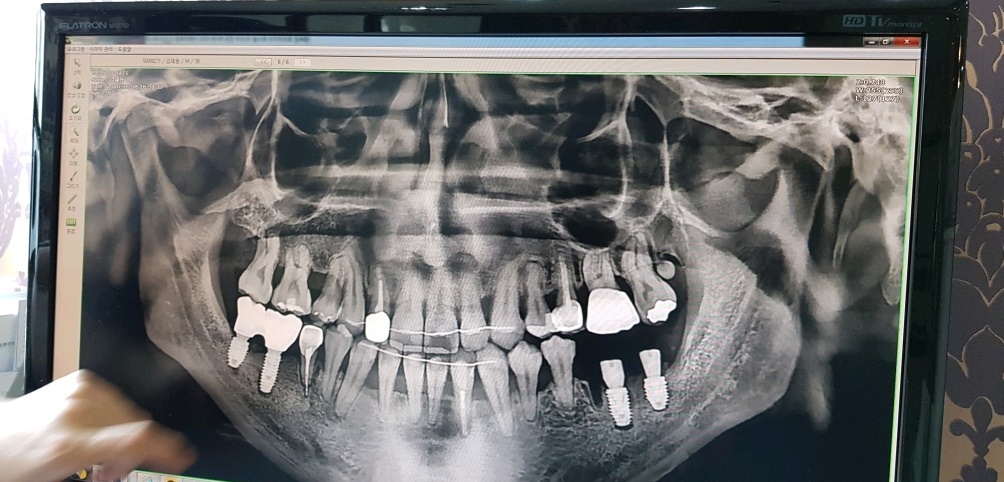

3년6개월에 거쳐 모든 과정이 끝난 지금의 내 치아상태인데

상악은 확실히 바뀐게 보이긴 한다..

그런데 밑의 앞쪽 치아들 중 한 치아는 강제로 이동되서 약간 비스듬히 뿌리가 잡혀있는게 보인다.

아마도 유지장치가 없다면 이 치아가 다시 원래자리로 돌아가겠지...

이제 교정이 끝나갈 무렵 어렸을 때(중딩시절) 주걱턱 교정 때문에 발치를 해야했던 하악 오른쪽 작은 어금니의 임플란트를 할 시기가 왔다...

해서 바로 시술 하려 했으나 양쪽해서 2개 박는데 320만원.... 거기다 뼈이식까지 포함하면 360;; 생각 했던 것 보다 가격이 많이 부담스러운 찰나 기억이 가물가물 한 치과에서 문자가 왔는데 임플란트 1개당 기본 76만원...? 상당히 파격적인 가격이라 방문하게 되었고, 상담결과 2개가 아닌 4개를 해야될 수도 있다고 한다;;

이유인즉슨 치아들끼리 양 옆으로 지탱해줘야 서로 튼튼한데 오른쪽 작은어금니를 뽑은지 너무 오래된 상태라(중딩때 주걱턱 교정때문에 멀쩡한 치아를 발치했었음) 어금니 뿌리가 잇몸에 살짝 걸쳐진 상태였고 치아교정때문에 부득이하게 치아가 하나 없는 상태임에도 와이어를 달고 무리하게 당겼기에 옆으로 임플란트를 하나 박는다 해도 어금니는 얼마못가 못쓰게 되서 뽑아야 된다고 한다.

지르코니아 임플란트 4개 + 뼈이식 = 302만원..?